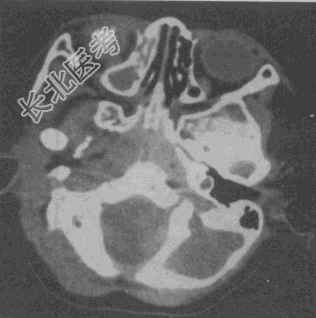

- 单项选择题女性,14个月。发现视力低下CT如图所示, 最可能的诊断是

A、脉络膜黑色素瘤

B、视神经胶质瘤

C、海绵状血管瘤

D、视网膜母细胞瘤

E、眼底出血